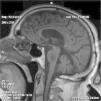

Síndrome confusional en paciente con hiponatremia severa